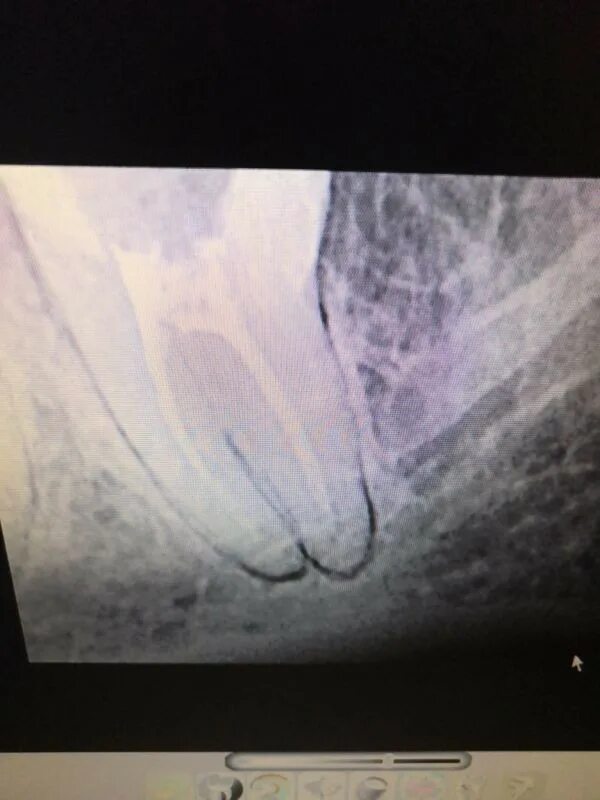

Как ощущается трещина